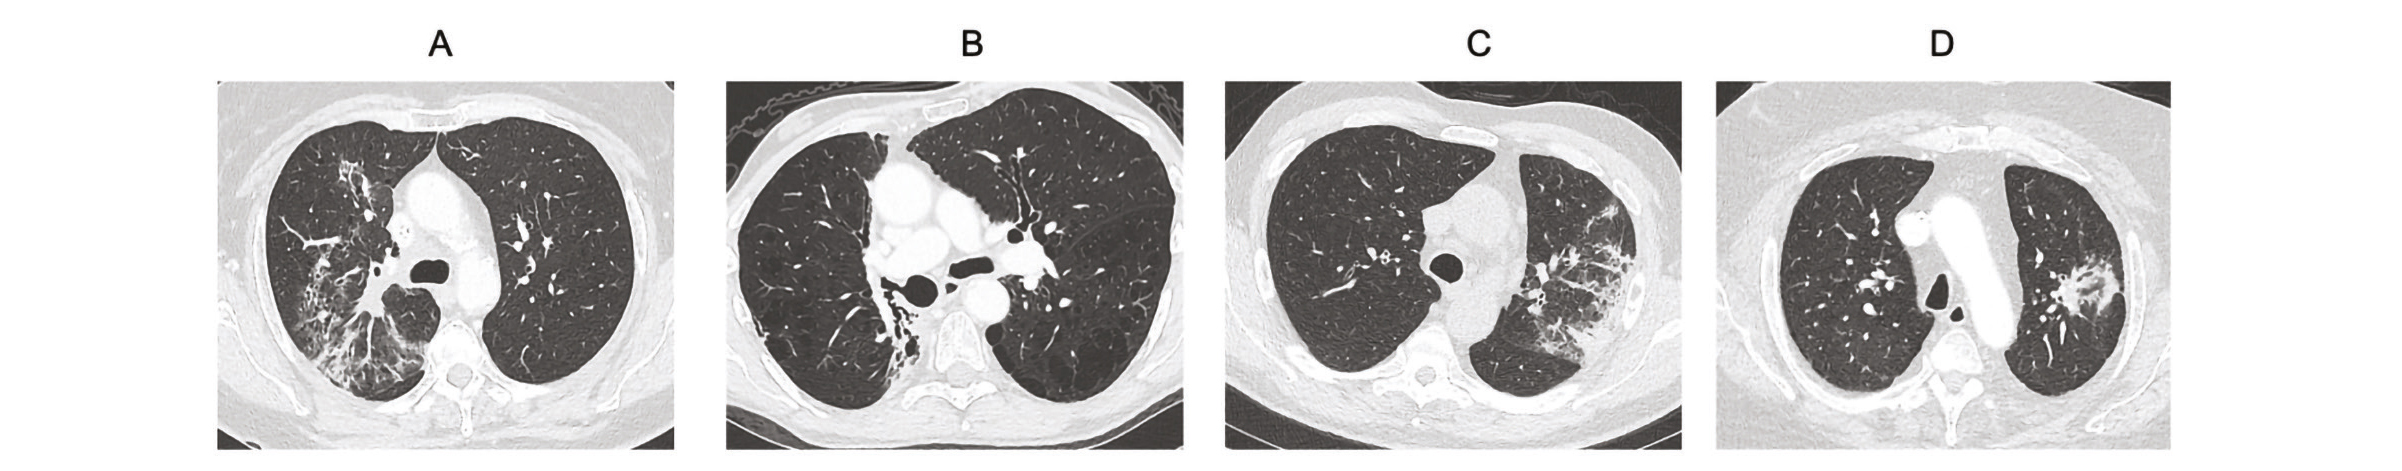

A, Pneumopathie radique aigue lobaire supérieure droite. B, Fibrose radique hilaire droite 8 ans après la fin de la radiothérapie.

C, Pneumopathie organisée après SBRT du lobe supérieur gauche. D, Remaniements radiologiques plusieurs années après SBRT

Deux caractéristiques majeures se dégagent sur l'imagerie :

- La RP est généralement limitée au champ d'irradiation et ne respecte pas les limites anatomiques (scissures ou lobes) (10).

La RP se manifeste par des opacités en verre dépoli, des condensations pseudonodulaires ou arciformes, ou encore des bronchectasies de traction, avec d'éventuels épanchements pleuraux, interlobulaires ou péricardiques.

Il n'existe aucune association évidente entre clinique et imagerie. Comme dans la RP, le scanner thoracique (CT) injecté est la technique d'imagerie de choix. Les principales anomalies radiologiques radio-induites sont des anomalies localisées dans les champs d'irradiation qui ne suivent pas la systématisation lobaire, avec des lésions se conformant aux isodoses (10).

La RF au CT se manifeste par des opacités rétractiles avec des signes de fibrose, des bronchectasies destructives, un épaississement pleural, une attraction de la trachée et du médiastin vers la région irradiée, et une perte de volume (14).

Les résultats au scanner thoracique (CT) injecté montrent des opacités alvéolaires, périphériques, sous-pleurales et migratrices. En effet, ces opacités sont initialement confinées à la zone irradiée avant de se propager au parenchyme non traité, ce qui différencie la pneumonie organisée de la RP.